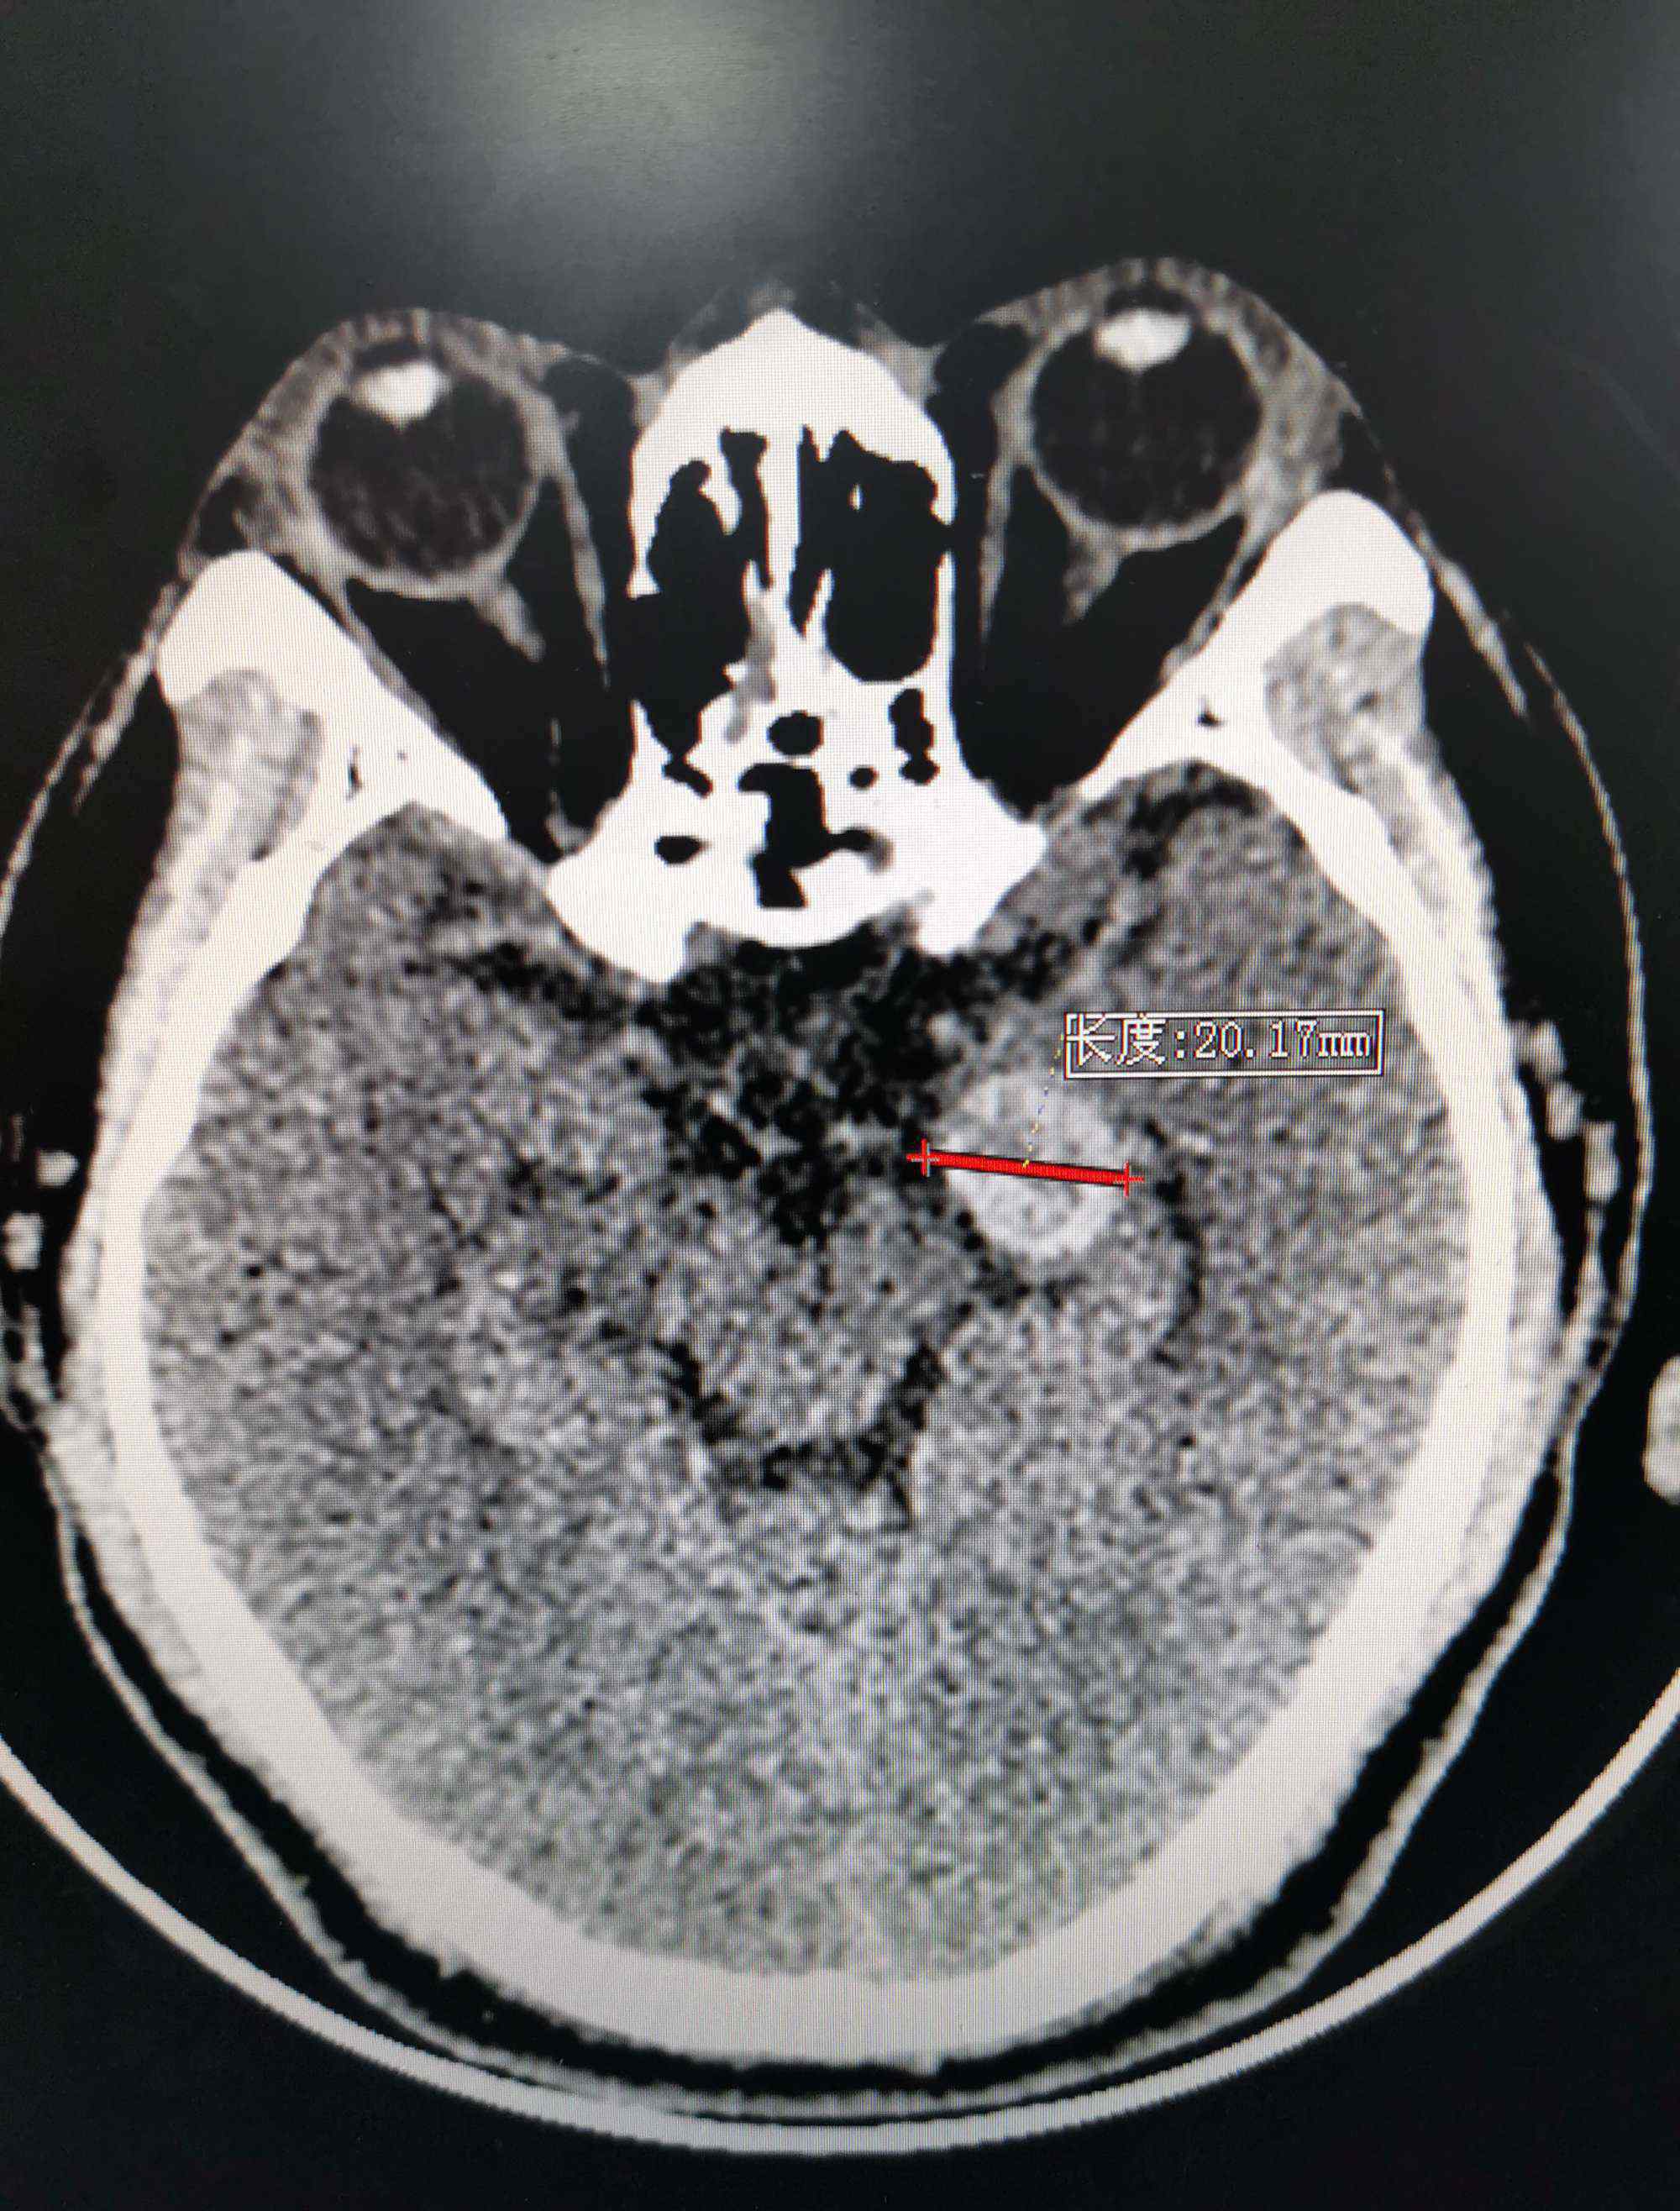

CT显示直径约为20毫米